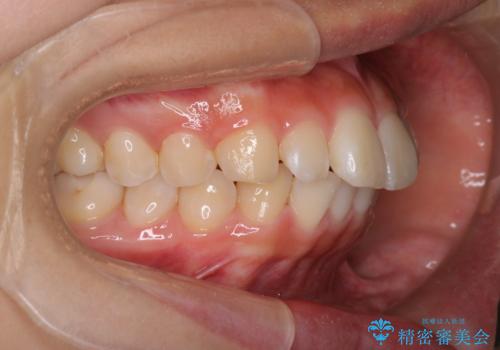

- ハーフリンガル

- 3年1ヶ月

- 出っ歯を治したいとのことで来院されました。

目立たない装置が希望とのことでハーフリンガルで治療をすることとしました。